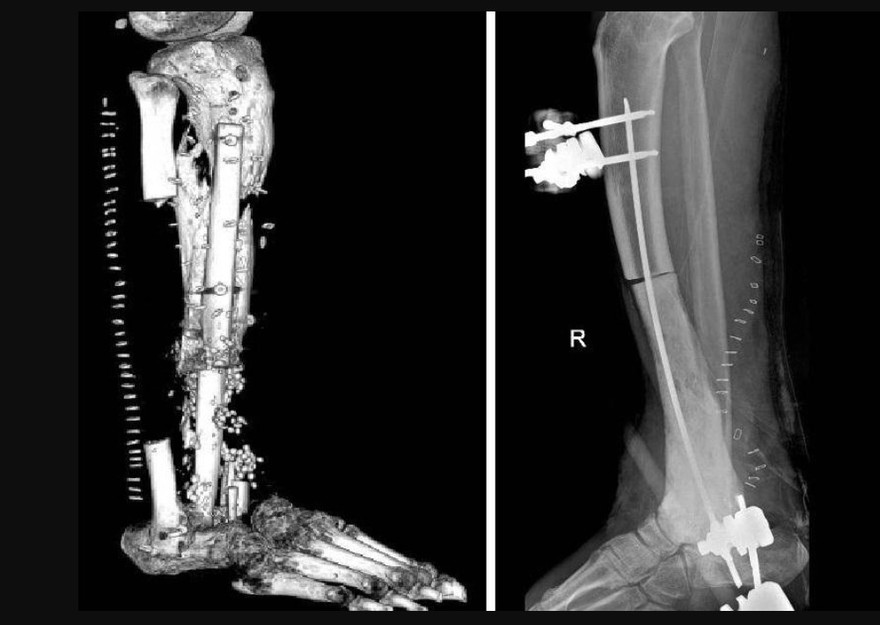

Spiega Perisano, ricercatore in Ortopedia e Traumatologia all'Università Cattolica del Sacro Cuore e dirigente medico presso la Uoc di Ortopedia e Traumatologia della Fondazione Policlinico universitario Agostino Gemelli Irccs: "In una prima fase abbiamo resecato quasi tutta la tibia del paziente sotto il ginocchio e l'astragalo, per rimuovere tutti i focolai di infezione. Successivamente abbiamo messo un sostituto temporaneo dell'osso, cioè uno spaziatore cementato e antibiotato, al fine di far guarire i tessuti e ridurre il rischio di re-infezione. Dopo 4 mesi di terapia antibiotica, abbiamo iniziato un percorso di ricostruzione ossea".

Inizialmente è stato fatto un tentativo di allungamento dell'arto con un fissatore esterno. "Si tratta di un intervento particolare - descrive l'ortopedico - consistente nell'osteotomia della parte di tibia rimanente e nella distrazione dei 2 monconi ossei (il gap osseo era di circa 20 cm), per permettere all'osso neoformato di crescere tra le porzioni di osso residue. In questo modo abbiamo recuperato 10 centimetri di osso; tanti, ma non sufficienti a ricostruire la parte mancante di tibia".

Illustra Pataia, docente di Chirurgia ortoplastica in Cattolica e chirurgo plastico nella Uoc di Ortopedia e Traumatologia del Gemelli: "Abbiamo effettuato una ricostruzione complessa prelevando 3 lembi, un muscolo-cutaneo dalla coscia e 2 ossei da entrambi i peroni del paziente. Successivamente, questa sorta di patchwork osseo-muscolo-cutaneo è stato collegato con tecnica microchirurgica. Si tratta di un sistema detto 'lembo-chimera', che consiste nel collegare un lembo muscolo-cutaneo al vaso arterioso della gamba ricevente, per poi collegare tra di loro i restanti lembi. In pratica il primo lembo alimenta l'altro, attraverso una serie di connessioni vascolari realizzate al microscopio, che partendo da un solo vaso ha consentito di alimentare 3 lembi diversi". Utilizzando infine il perone della gamba sana e quello della gamba malata, Perisano ha ricostruito la parte mancante della tibia e l'astragalo del paziente, fissando il tutto con delle viti ortopediche e mettendo a protezione un fissatore esterno circolare, per permettere la guarigione dei tessuti e far consolidare le parti ossee.